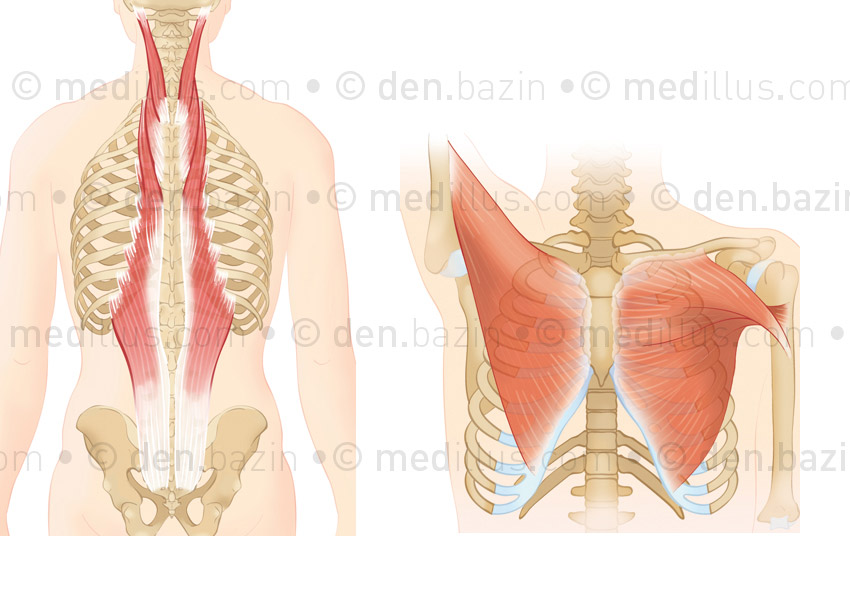

Muscles dorsaux et grand pectoral